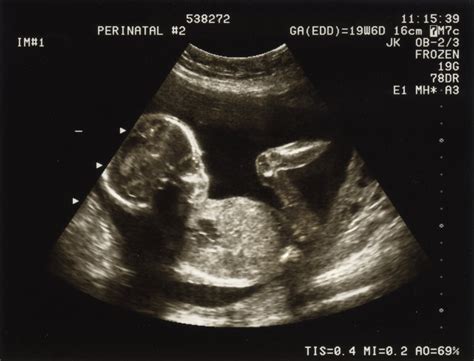

La gravide, la prima ecografie se urmăreşte: stabilirea existenţei, localizării, viabilităţii, vârstei cronologice a sarcinii, depistarea modificărilor patologice asociate (decolarea sacului ovular, uter fibromatos, chist luteic, sarcină ectopică etc).

La 12-13 săptămâni, la 30-31 săptămâni, la 36-37 de săptămâni de sarcină scopul ecografiei este de a confirma aşezarea fătului, poziţia craniului fetal şi de a obţine date despre mărimea şi starea de sănătate a fătului.